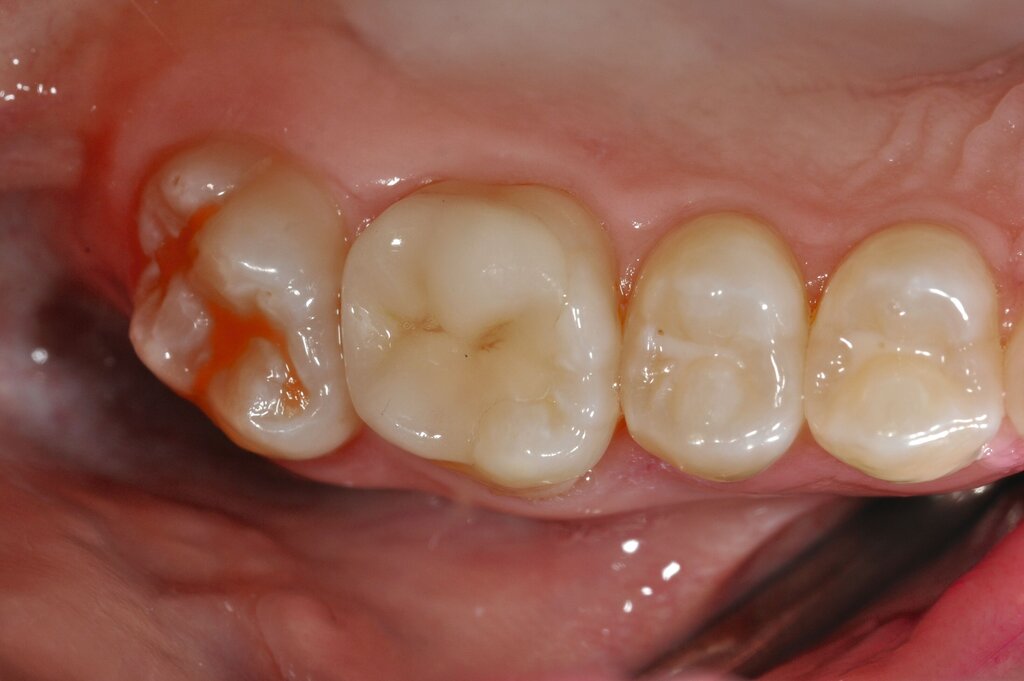

Der Vorteil der Methode ist, dass die betroffenen Zähne auch ohne Lokalanästhesie und Präparation versorgt werden können. Die temporäre Versorgung ermöglicht es, die Patienten an die zahnärztliche Behandlung zu gewöhnen. Häufig führt diese temporäre Versorgung auch zu einer Reduktion der Hypersensitivität der MIH-Zähne. Nachteil der GIZ-Versorgung ist das Risiko einer Füllungsfraktur oder eines vollständigen Verlusts der Füllung (Abbildung 4). Aktuelle Erhebungen bestätigen eine Erfolgsrate von über 80 Prozent nach einem bis zwei Jahren [Durmus et al., 2021; Mahfouz et al., 2025].

Der Behandlungsfall (Abbildung 4d) veranschaulicht die Schwächen des Verfahrens. Wird das Angebot der regelmäßigen Kontrollen nicht wahrgenommen, so droht bei Verlust der Füllung die Kariesprogression. In dem vorliegenden Fall konnte jedoch eine endodontische Maßnahme vermieden und durch die selektive Kariesentfernung die Zahnhartsubstanz weitestgehend erhalten werden.